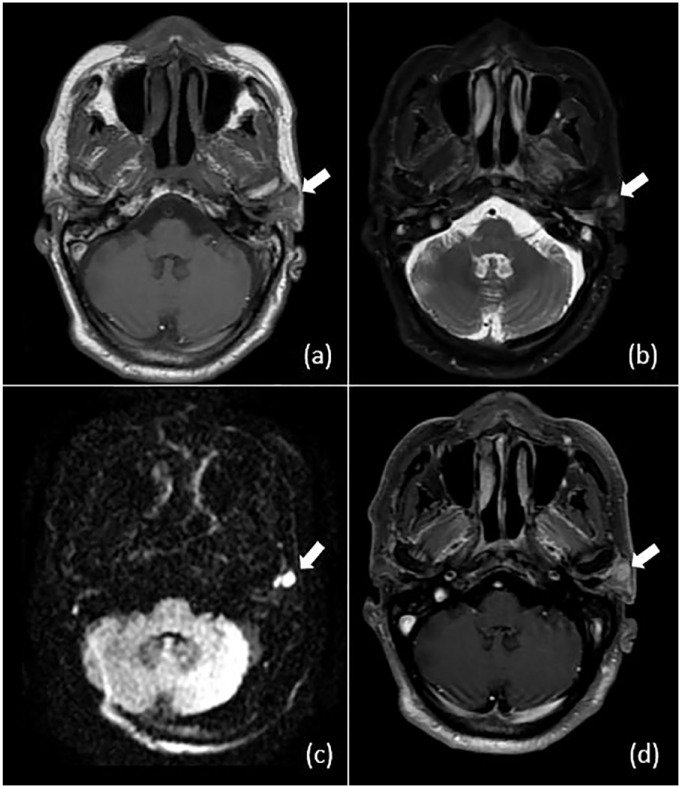

Case presentation: A 57-year-old male patient of north African origin presented with a left parotid mass that had been evolving for 6 months. He was previously diagnosed with and treated for nasopharyngeal carcinoma 2 years prior to admission, with Intensity-Modulated Radiotherapy (IMRT) without sparing the parotid gland, as well as chemotherapy. Medical imaging was suggestive of recurrence of nasopharyngeal carcinoma and metastasis due to the patient's medical history. The patient benefited from a total parotidectomy; The histopathological analysis of the surgical specimen confirmed the presence of a poorly differentiated carcinoma (UCNT) with nodal metastasis.